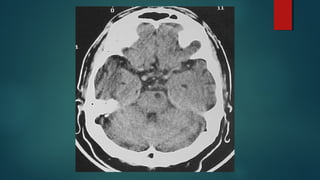

Este documento es el programa para un taller de imágenes del curso de emergencia 2015 impartido por el Dr. Víctor Delgado. El taller se centra en el uso de imágenes médicas para el diagnóstico y tratamiento de pacientes en coma traumático según la base de datos de Marshall. El Dr. Delgado es el único instructor repetido a lo largo del documento.